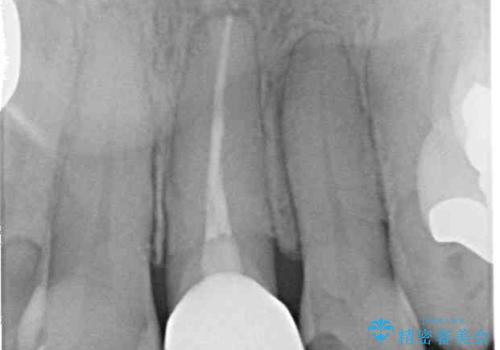

口元を引っ込めることができたため、口を閉じるときに力が入っていて皺のよっていた顎先も、スムーズに閉じられるようになったことで力がかからなくなりました。

変色して気になっていた前歯も、オールセラミッククラウンで自然な色合いにすることができました。